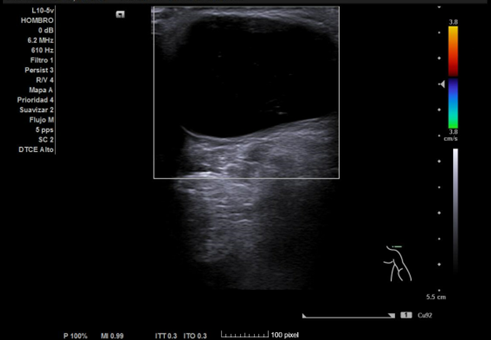

Ecografía hombro izquierdo: se observa una masa de 2,3 x 3,4 cm, anecoica en su totalidad, no tabicada, de bordes bien definidos y sin captación en Doppler.

Diagnóstico final: quiste sinovial probablemente perteneciente a la articulación acromioclavicular.